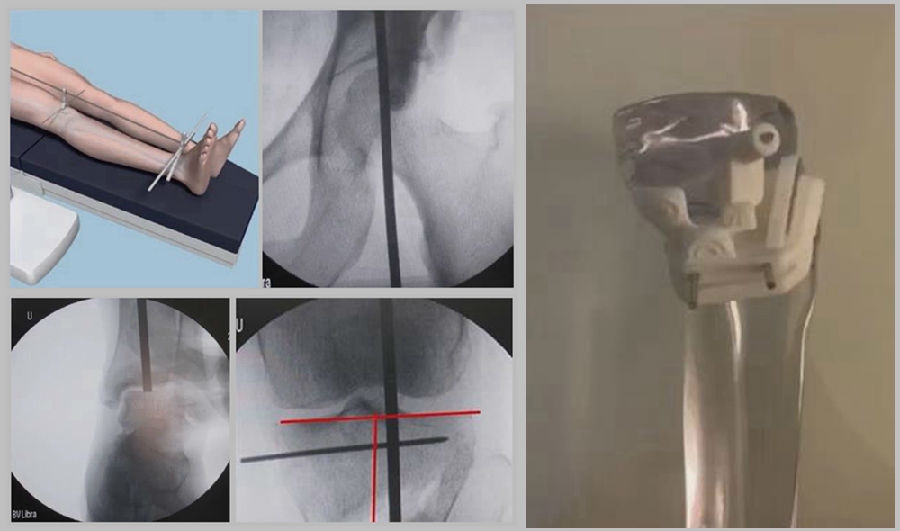

1、综合判断力线的方法

现在对于力线的判断大致通过以下几方面:①大体形态;②透视确定力线,连接股骨头中心、踝关节中心,看力线杆和膝关节中心的位置关系;③MPTA(胫骨平台关节线和胫骨侧机械轴夹角);④PSI。

1、原因及预防

(1)肢体外旋

一般来说在麻醉状态下肢体会处于外旋位,此时去测定力线的话往往需要将肢体放在旋转中立位,但是在内旋肢体的过程中会出现内翻应力,那么这种情况下判断力线会带来误差,所以通常建议大家要把手术床做一点旋转,让患肢处于自然的旋转中立位,这样再去判断力线就比较准确。

(2)MCL浅层未彻底松解

对于MCL,大多数忽视的是后侧束,如果不能把后侧束彻底松解,那么在撑开过程中往往会感觉撑不开,此时如果过度去撑开的话,会导致在关节内侧出现很大的压力,所以这时对力线会产生一定的误导。

(3)力线验证未模仿负重应力

现在所谓的目标力线应该是模仿负重时的力线。做截骨时,通常会将力线轻度外移,如果没有考虑关节内畸形、韧带松弛或是软骨磨损,那么在负重时,在内侧副韧带撑开过程中,会出现力线偏移。所以要注意,手术中间在调整目标力线时,要以应力状态下为标准。

(4)拉力螺钉加压过度

拉力螺钉的过度使用可能会引起矫形位置的角度丢失。当拉力过度时,会将力线由内侧向外侧轻度拉回,使力线丢失一部分,所以切忌过度使用。